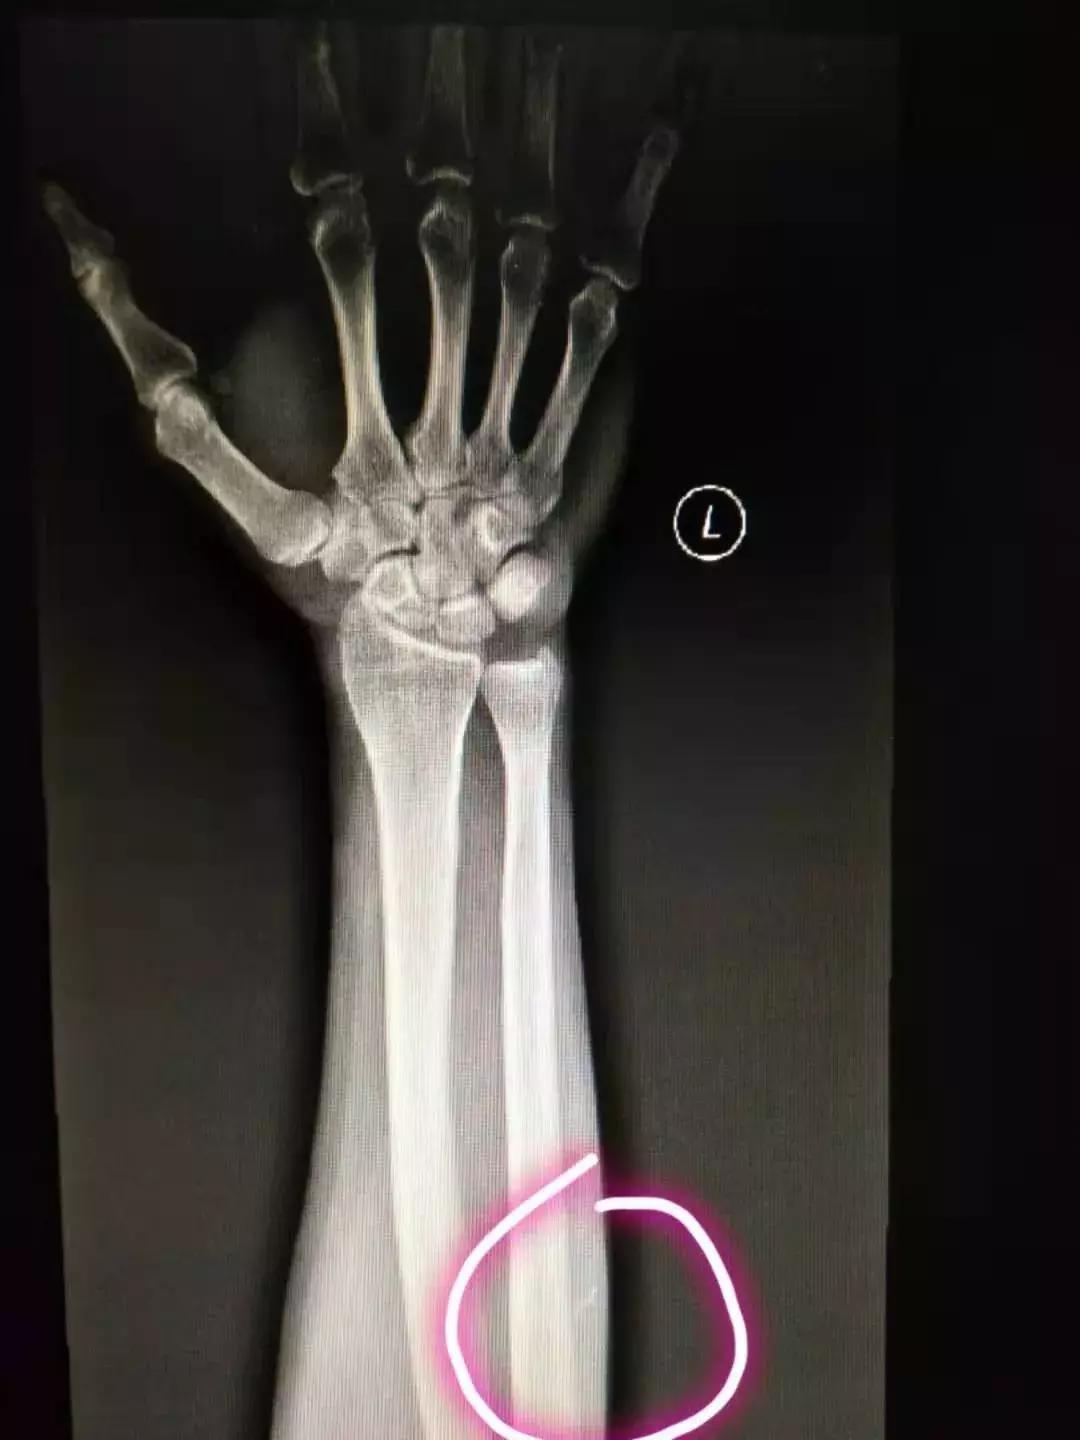

30分钟后,影像系统查看到患者X线片,弯曲金属物体!

接诊医师阅片后,决定局部麻醉下取出异物。09:30异物取出,患者表示感谢!